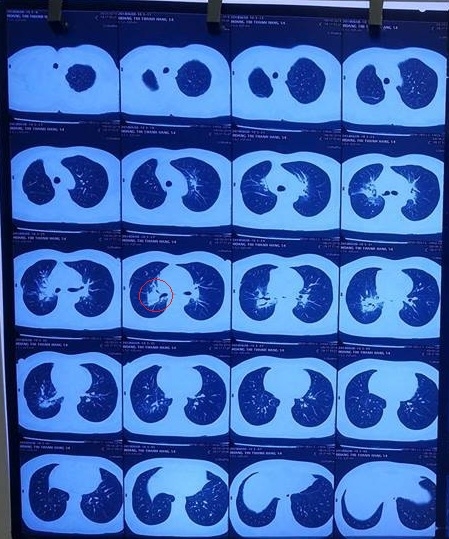

2. HOÀNG THỊ MINH HẰNG: Nữ, 54 Tuổi. Địa chỉ: Hải An – Hải Phòng

- Bệnh nhân phát hiện ung thư phổi phải tháng 8/2017, đã phẫu thuật và truyền hóa chất tại BV K. Kết thúc điều trị tháng 10/2018

- Sau điều trị BN còn ho nhiều, đau tức ngực, mất ngủ, mệt nhiều.

Chụp CT(4/2018): Tổn thương đông đặc nhu mô vị trí rốn phổi phải.

- Tháng 4/2018 BN uống Kilcel 500mg, sau uống 1 tháng đỡ ho, đỡ đau, ngủ được, đỡ mệt nhiều. Sau uống 2 tháng hết ho, không đau tức ngực, ăn ngủ tốt, tăng cân.

Chụp CT(6/2018): Còn tổn thương vị trí rốn phổi phải, kích thước giảm nhiều so với kết quả chụp trước khi uống Kilcel 500mg

Hình ảnh chụp CT phổi trước khi uống Kilcel 500mg